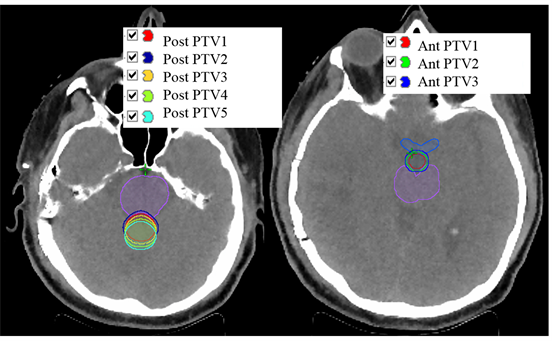

The head and neck Alderson Rando anthropomorphic phantom (Model# ART 210: RSD Alderson Phantoms, Long Beach, California) was scanned axially using our in-house CT-SIM (Siemens Medical Solutions USA, Inc.) both horizontally and vertically (120 KVp, 200 mAs, 515 × 515 matrix size, 50 cm field of view, and 2 mm slice thickness) and exported to the Eclipse Treatment Planning system (Version #15.6, Varian Medical Systems, Palo Alto, CA) for treatment planning. PTVs were selected to simulate conditions where the cARC technique might be particularly advantageous as indicated in Figure 1. The PTVs were contoured posterior to the brainstem (Post PTVs) and centrally between the brainstem and optic chiasm (Ant PTVs). The set of “Ant PTVs” and “Post PTVs” were drawn to evaluate the effectiveness of cARC delivery. Varying distances from OARs (i.e. brainstem and/or optic chiasm) were used for each set of PTVs to assess the potential benefits of the cARC technique. The naming convention and descriptions for all PTVs are provided in Table 1.

Figure 1. Simulated planning target volumes with incremental margins near organs at risk. “Post PTVs” (Left Panel) is located posterior to the brainstem. “Ant PTVs” (Right Panel) is located in between the optic chiasm and the brainstem.